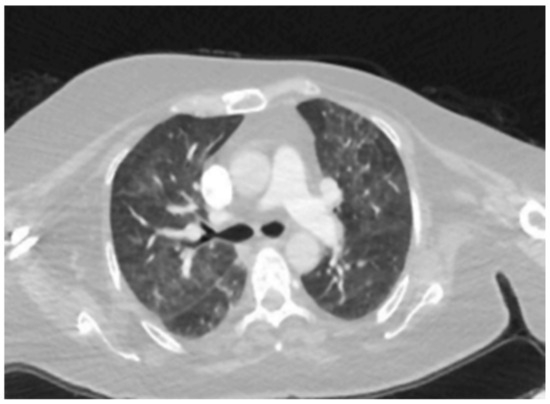

| Patient 9 | Acute Interstitial Pneumonia/ARDS (AIP-ARDS) | Palbociclib | Ground-glass opacities, |

| consolidations, and honeycombing. (Figure 4) | |||